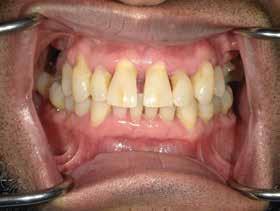

Issuu converts static files into: digital portfolios, online yearbooks, online catalogs, digital photo albums and more. Sign up and create your flipbook.